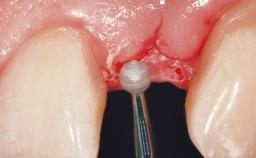

Bone Augmentation Horizontal|Staged

Augmentation Materials Autogenous chips|Membrane

Soft Tissue Grafting Simultaneous